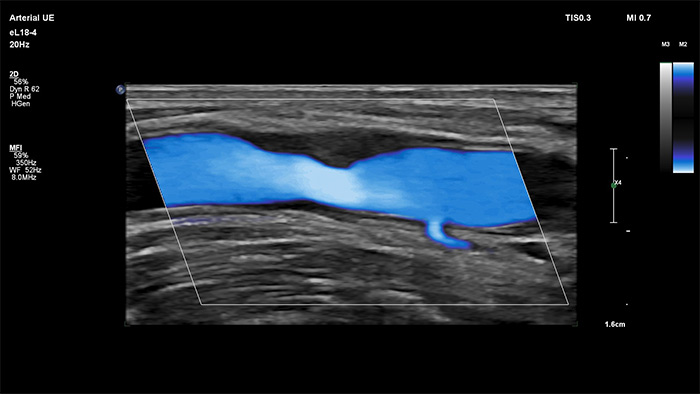

Philips MicroFlow Imaging è concepito per rilevare con considerevole sensibilità il flusso di sangue lento e debole nei tessuti e migliorare la risoluzione del flusso in esami vascolari. Grazie alla risoluzione elevata e agli artefatti ridotti al minimo, i medici sono in grado di visualizzare e caratterizzare piccole alterazioni del flusso attorno alla placca stenotica per formulare diagnosi affidabili.